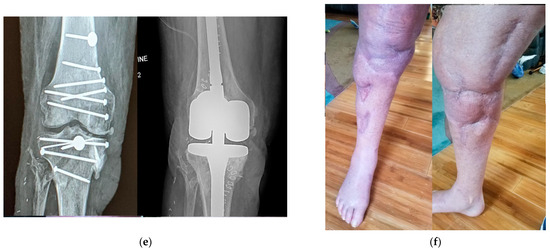

3.3. Applications on Lower Extremities Reconstruction